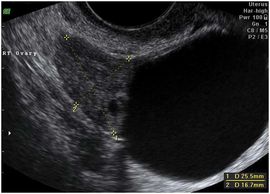

Polycystic ovarian syndrome (PCOS) is a common hormonal condition and deserves special mention. Patients with PCOS have a hormonal imbalance that can result in irregular periods, few periods (oligomenorrhea) or no periods (amenorrhea). They have high levels of Luteinizing hormone (LH), which leads to anovulation, and may lead to high levels of insulin and testosterone, Patients may have hirsuitism (excess hair growth) and acne. The typical 'cysts' are multiple small follicles, usually less than 10 mm, arranged in a peripheral location. Patients with PCOS may have superimposed other conditions including symptomatic functional cysts, so the presentation is not always clear.

Typical PCOM